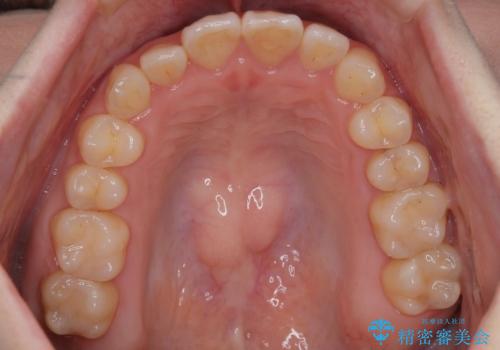

【インビザライン】前歯のがたつきを目立たない装置で治療

- 前歯の叢生を主訴に来院されました。目立たない装置を希望されたためインビザラインで治療を行いました。

IPRと拡大をし、叢生を治しました。右上2番は反対咬合でしたが短期間できれいに治りました。